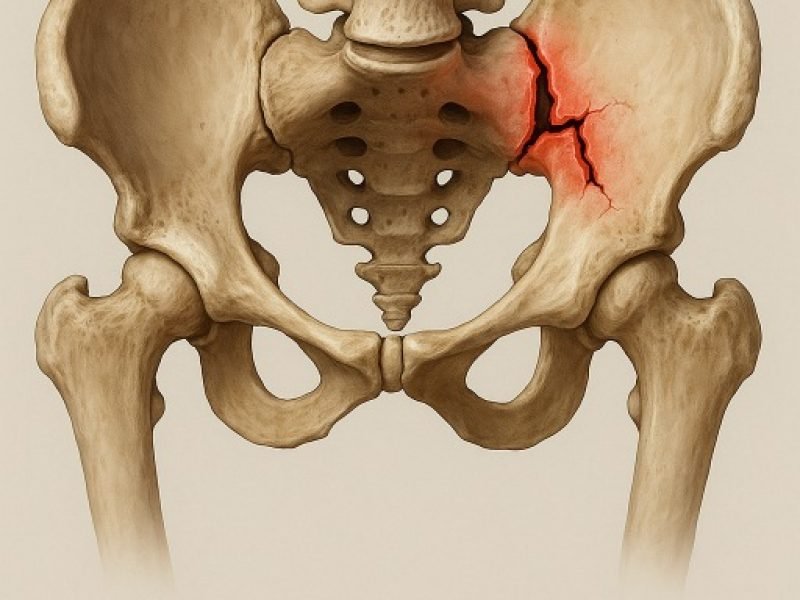

We provide specialized surgical care for pelvic injuries, using precise techniques to stabilize the pelvic structure and promote a safe, complete recovery.